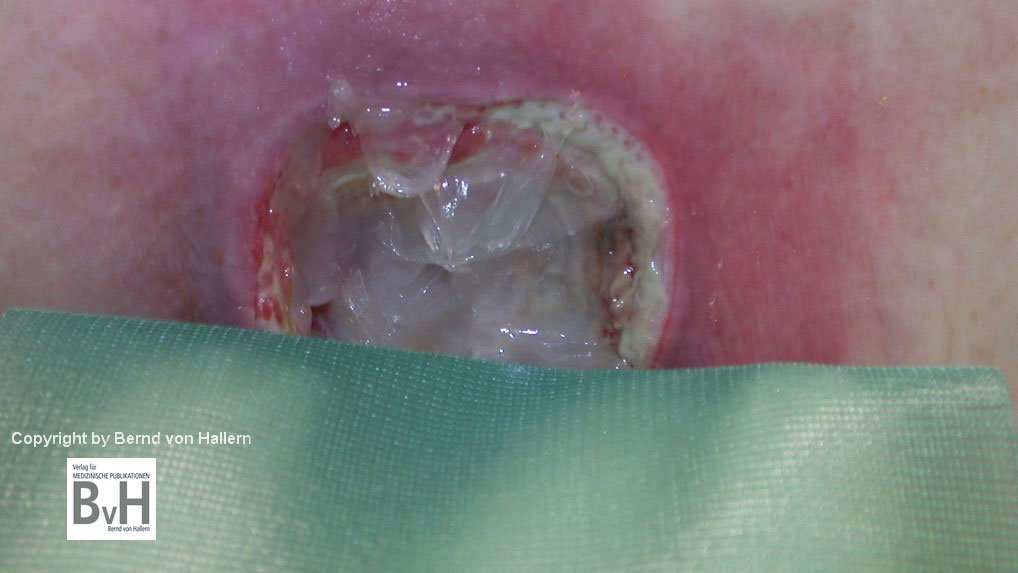

Schädlich für die Wundheilung, besser nicht benutzen

Bild 3: Nach H2O2- Spülung zeigt sich ein weißer Wundgrund durch oxidierte Zellen.